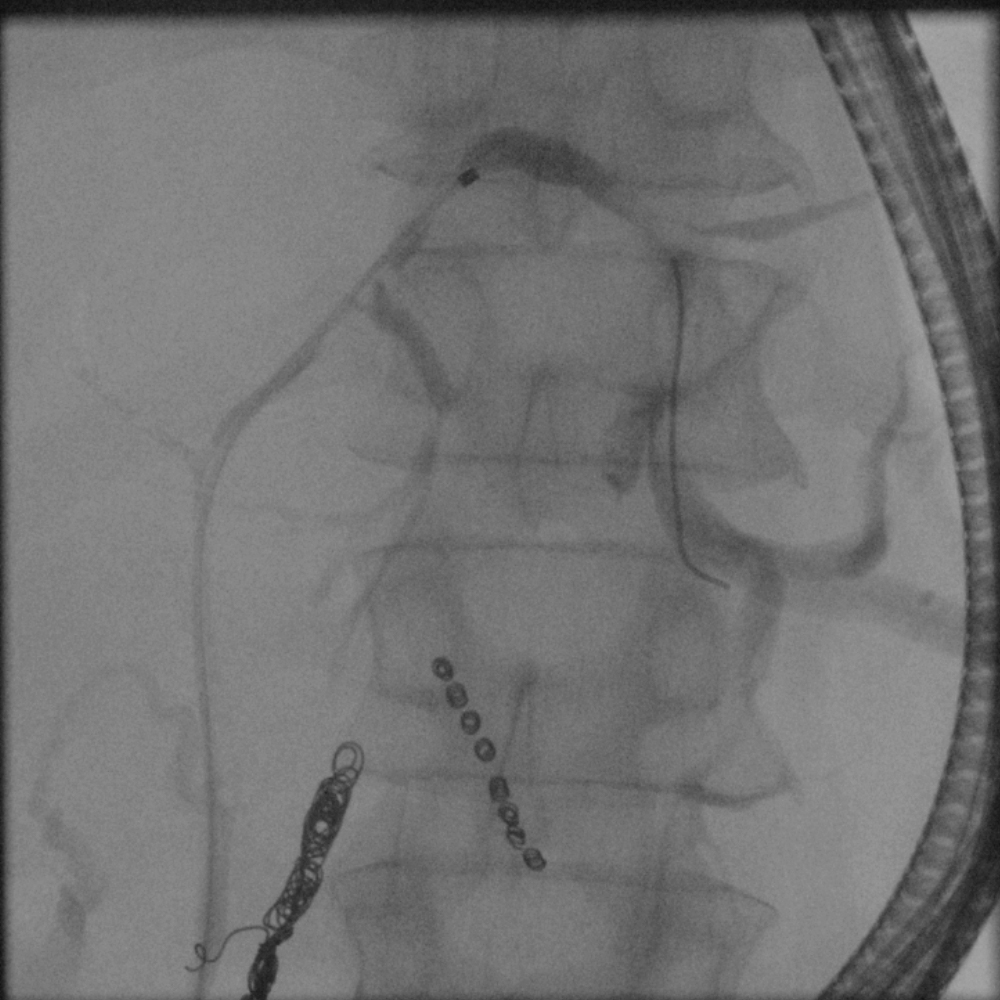

2. Targeted selective cannulation of both hepatic ducts in cases of Klatskin tumors.

Case 2